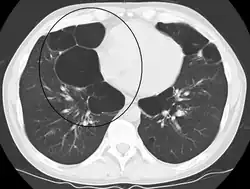

A chest X-ray and complete blood count may be useful to exclude other conditions at the time of diagnosis.[82] Characteristic signs on X-ray are hyperinflated lungs, a flattened diaphragm, increased retrosternal airspace, and bullae, while it can help exclude other lung diseases, such as pneumonia, pulmonary edema, or a pneumothorax.[83] A high-resolution CT scan of the chest may show the distribution of emphysema throughout the lungs and can also be useful to exclude other lung diseases.[25] Unless surgery is planned, however, this rarely affects management.[25] A saber-sheath trachea deformity may also be present.[84] An analysis of arterial blood is used to determine the need for oxygen; this is recommended in those with an FEV1 less than 35% predicted, those with a peripheral oxygen saturation less than 92%, and those with symptoms of congestive heart failure.[24] In areas of the world where alpha-1 antitrypsin deficiency is common, people with COPD (particularly those below the age of 45 and with emphysema affecting the lower parts of the lungs) should be considered for testing.[24]

A severe case of bullous emphysema -

Axial CT image of the lung of a person with end-stage bullous emphysema -